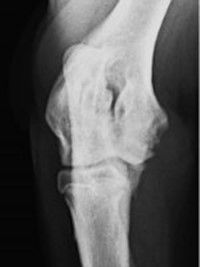

Queste malattie ereditarie colpiscono molte razze canine durante la crescita, causando dolore e riducendo la qualità della vita. La displasia dell’anca è una malformazione in cui la testa del femore non si adatta perfettamente alla cavità del bacino, mentre la displasia del gomito comporta una crescita disarmonica delle ossa che compongono l’articolazione.

Le displasie possono essere diagnosticate precocemente con esami radiografici eseguiti dal quinto/sesto mese di vita. Questi esami, effettuati in sedazione, includono proiezioni specifiche per anca e gomito e sono essenziali per intervenire tempestivamente.

Nello specifico lo studio dell’anca prevede ben 4 proiezioni (antero posteriore standard, in distrazione, a rana e dar).

Lo studio del gomito prevede due proiezioni (latero /laterale e antero posteriore).